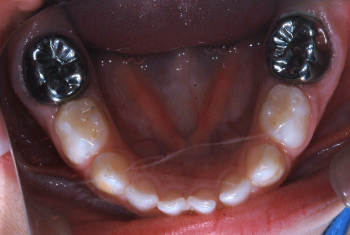

Odontopediatría

Caso 1